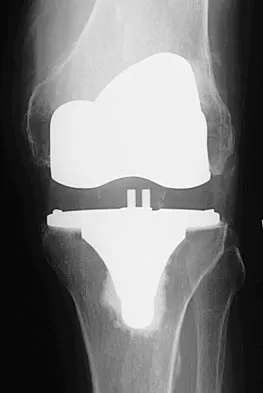

An obese patient undergoing total knee arthroplasty is at increased risk for which of the following complications?

Explanation

The rate of wound complications is significantly increased after total knee arthroplasty in obese patients. Knee scores and the rate of aseptic loosening or patellar subluxation do not appear to be significantly altered. Winiarsky R, Barth P, Lotke P: Total knee arthroplasty in morbidly obese patients. J Bone Joint Surg Am 1998;80:1770-1774. Stern SH, Insall JN: Total knee arthroplasty in obese patients. J Bone Joint Surg Am 1990;72:1400-1404.